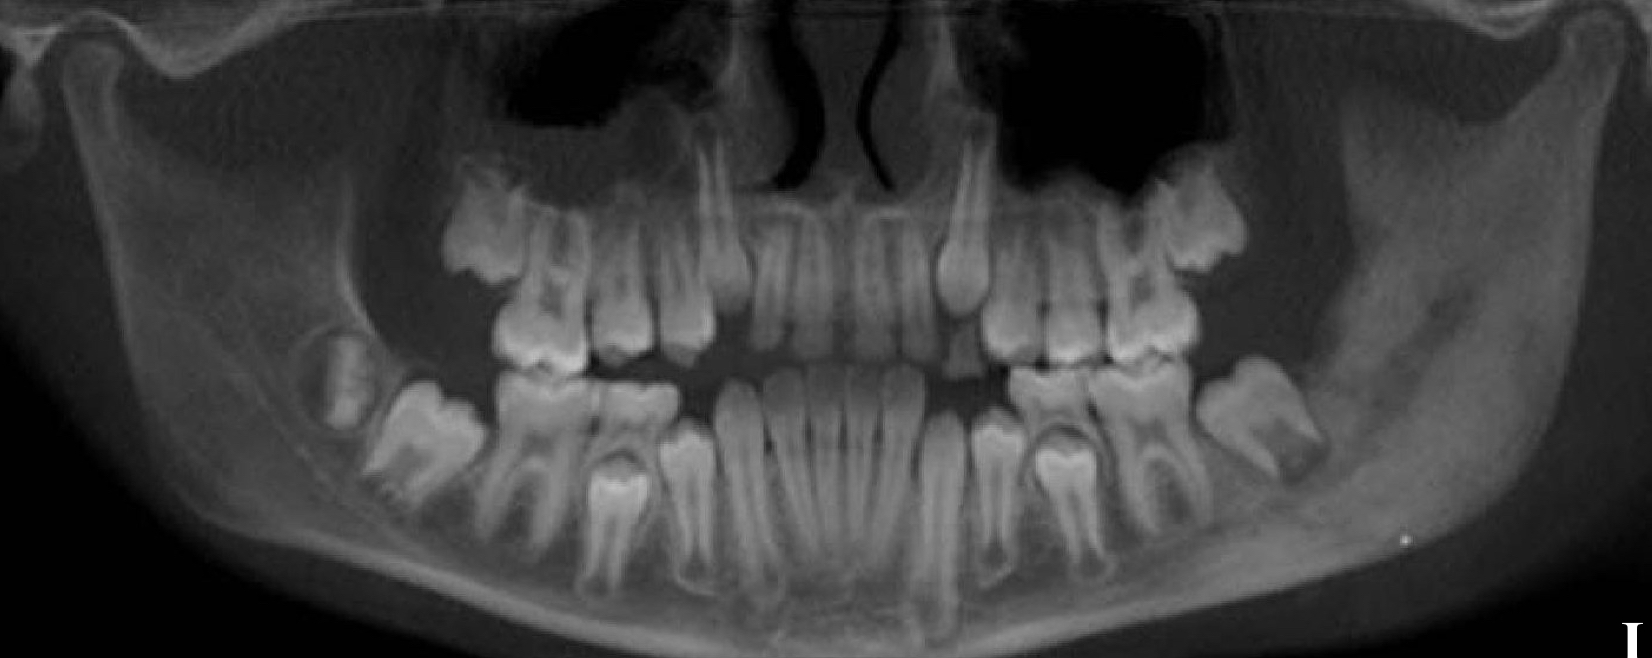

which osteomyelitis phase?

periphery:

poorly defined

non-corticated

gradual transition to normal trabeculae

acute

internal structure:

decrease in bone density, loss of sharpness of trabeculae

localized or scattered regions of radiolucency, ill defined periphery

mixed radiolucent-radiopaque areas

“moth-eaten”

irregular outline

help: mandibular trabeculae looks like lasagna but here more granular and indistinct